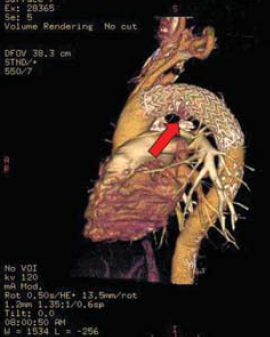

4. ábra.

PAU az aortaíven.